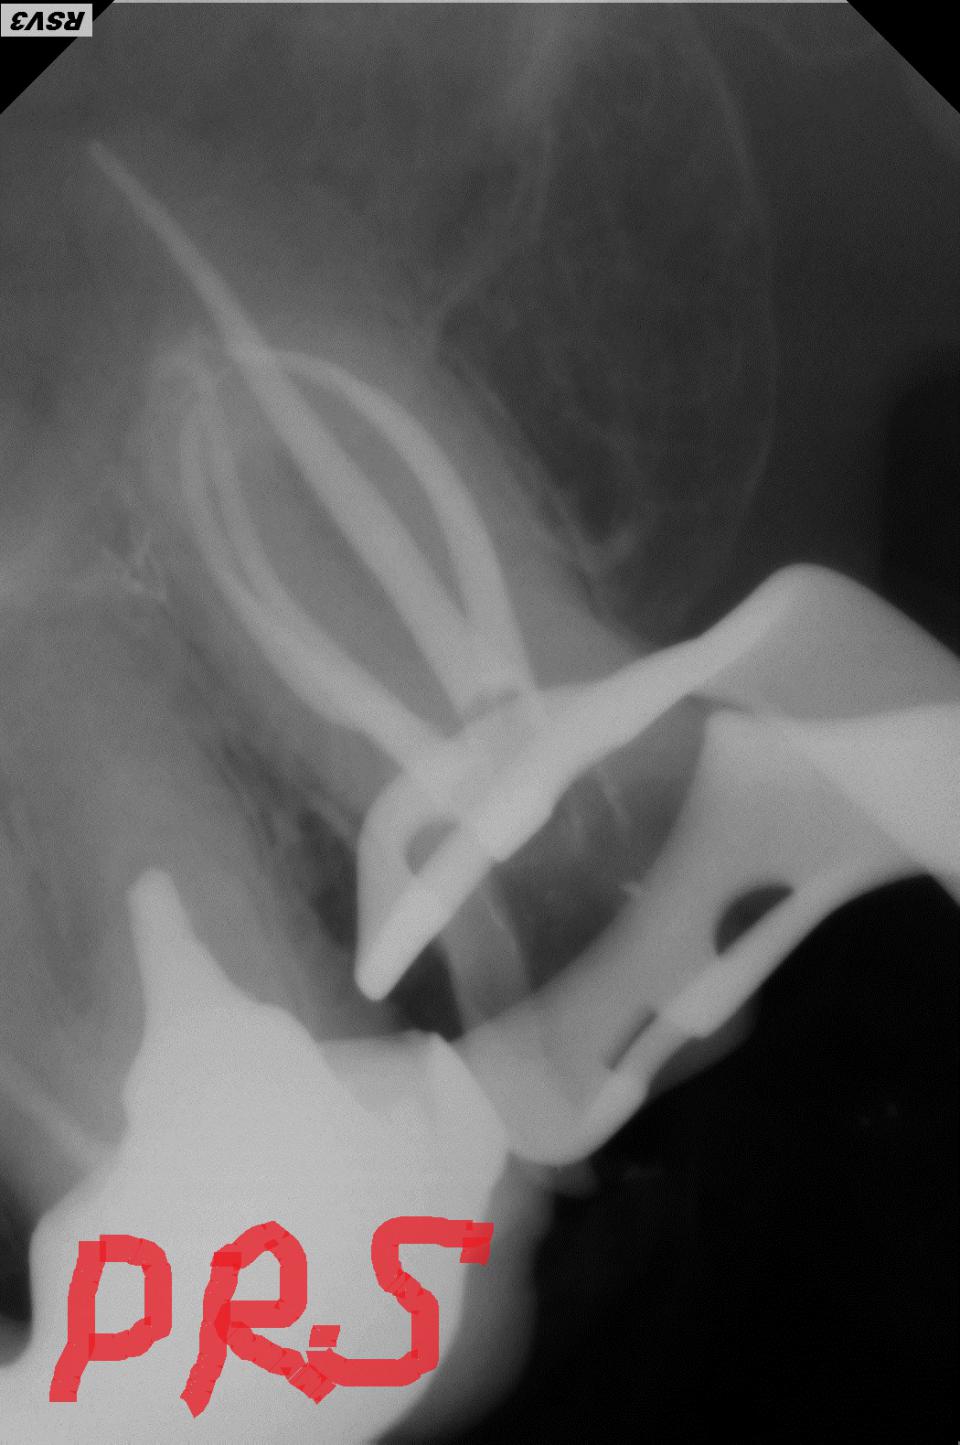

paraschyk1 Опубликовано 8 августа, 2013 Автор Опубликовано 8 августа, 2013 Ой AT0N,беги. Беги к другому спецу. 1.Если зуб со всех сторон разрушен и во множестве пломб,плюс уже депульпирован (удалены нервы)-это коронка. 2.За 30гр будет скорее всего самый дешевый анкерный (металлический штифт),потому как стекловолокныый штифт (СВШ) по 15-60гр/штука в закупке. Большая половина докторов,к тому же,не умеет правильно фиксировать СВШ. В таких руках лучше будет работать анкерный. 3.Конструкция эта (хим.ком + мет.штифт) гуано,так как долго держать герметизм не будет и гнить начнет под ней. Фото.пол+мет.штифт получшее. 4.Врач который делает такие сравнения и выводы о пломбировочных мат-лах,пардон,но профан. Даже сами фотополим. в зависимости от своей наполненности разной прочности. Предложила она тебе хим.комп потому,что ей проще им зашпаклевать зуб,чем лепить из фото. Исходя из изречений лечащего тебя врача,назрел вопрос о адекватности пломбировки корневых каналов (к/к). Если снимок у тебя можешь сравнить с ниже представленными. В 6х и 7х зубах в основном (70-80%) 4ре к/к,бывает и 5ть. На снимках как раз можешь видеть такие случаи. Но если твой врач хотя бы три канала,сравнительно так,запломбировала можно что-то думать дальше. Если нет,айда по новой. На твоем месте я бы восстанавливал зуб коронкой.